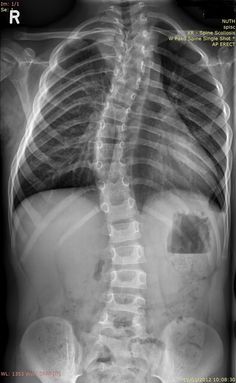

척추 측만증이나

거북목, 일자목 같은 문제가 있는

아이들은

실제 키보다 더 작게 보입니다.

이러한 경우

뭉쳐있는 근육을 이완하고

틀어진 뼈를 제 위치로 바로잡는

추나 요법을 병행하여

숨어있는 키를 찾아드리고 있습니다.